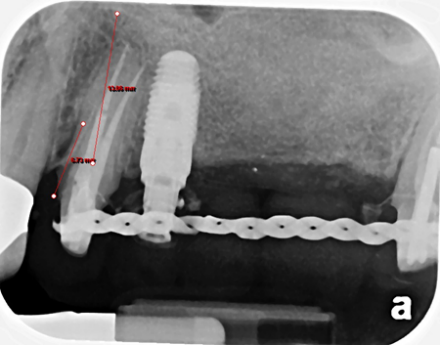

When there’s no available bone beneath the sinus floor (Fig. 1), we perform a full (external) sinus lift. We elevate the Schneiderian membrane and pack in bone graft material (Fig. 2). After 6-9 months, the new bone allows implant placement (Fig. 3). Four months later, those implants are restored with abutments and crowns (Fig. 4).

Fig. 2: Bone Filled-In Below Sinus Membrane Using a Full (External) Sinus Lift Process